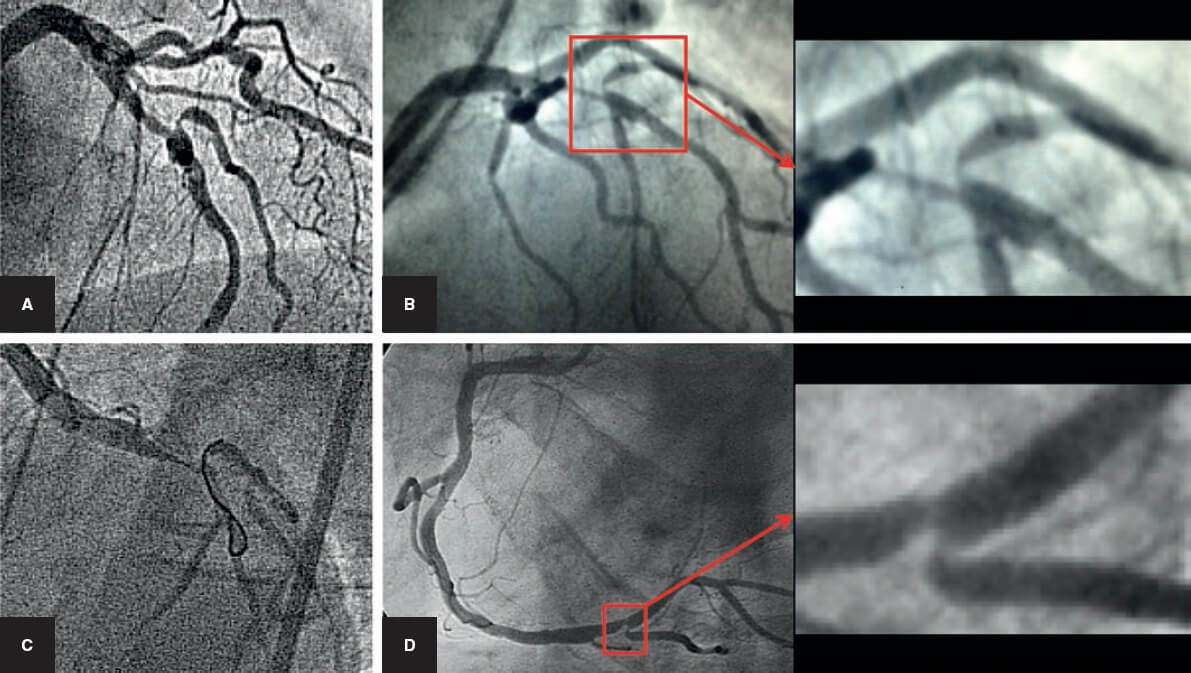

Acceso difícil a la rama lateral

Esta circunstancia sigue constituyendo un problema en el tratamiento de las bifurcaciones. Angulaciones excesivas, calcificaciones y lesiones difusas pueden impedir la introducción de la guía en la RL (figura 4). La situación se agrava una vez implantado el stent del VP, por la interposición de una capa de metal y por el aumento de la estenosis o incluso su cierre en el origen de la RL. Para resolverlo se han diseñado dispositivos específicos y técnicas ingeniosas de wiring de la RL. Entre los nuevos dispositivos se encuentran los microcatéteres con punta deflectable o muy angulada23 que se orientan hacia el origen de la RL. Los catéteres de doble luz permiten el uso de una guía muy angulada por la salida lateral, pudiendo avanzar y retroceder con todo el sistema hasta «enganchar» el origen de la RL24. Esto en ocasiones es muy difícil y constituye en la actualidad un problema no resuelto en un pequeño porcentaje de los casos.

Figura 4. Acceso difícil a la rama lateral. A, B y C: arteria descendente anterior/diagonal. D: coronaria derecha/descendente posterior. A la derecha: detalle ampliado del ángulo de la bifurcación.

Otra situación que también se considera una indicación de técnicas de 2 stents desde el principio es la presencia de una lesión larga o difusa en una importante RL. En estos casos se asume que la angioplastia con balón no va a tener un buen resultado (figura 5).

Por último, la restenosis de la RL tras un procedimiento simple también merece el tratamiento con un segundo stent en la RL (figura 6)43.

Figura 5. Bifurcación en la descendente anterior con lesión difusa en la rama lateral. Técnica de 2 stents desde el comienzo (cullotte). A: angiografía basal. B: resultado final. C: imagen en vacío de los 2 stents.

Figura 6. A: reestenosis difusa del origen de la arteria circunfleja después del tratamiento con stent provisional del tronco de la coronaria izquierda. Tratamiento con un segundo stent (T y protrusión en 2 tiempos). B, C y D: stent boost del tronco común durante los diferentes pasos de la técnica.